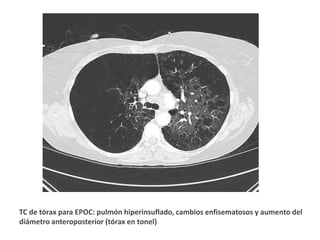

TC de tórax para EPOC: pulmón hiperinsuflado, cambios enfisematosos y aumento del

diámetro anteroposterior (tórax en tonel)

TC de tóraxpara EPOC: pulmón hiperinsuflado, cambios enfisematosos y aumento del diámetro anteroposterior (tórax en tonel)